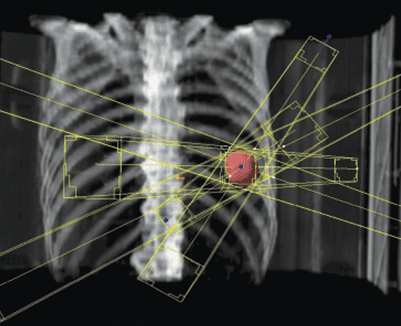

Stereotactic refers to the use of a specifically designed coordinate- system to locate small targets inside the body. This specialized form of radiation involves the use of multiple, highly precise radiation beams to safely deliver high doses of radiation to the tumour, with very sharp dose gradient outside the tumor and the surrounding normal tissue, in a manner not achievable by standard conventional radiation therapy.

The ability to deliver SBRT has been made possible by the use of better quality imaging e.g. CT scans, PET, MRT as well as other advanced imaging platforms to localize the tumor in four dimensions. Unlike tumours in the brain, tumours in the body can move with respiration which has to beaccounted for.